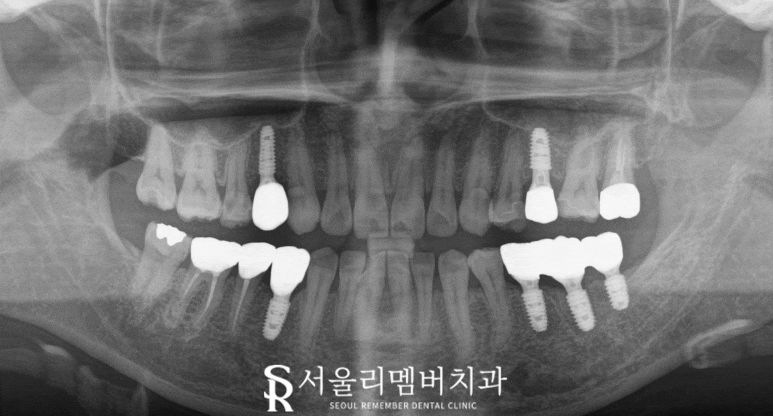

2023.09.29

비어있던 곳이 채워지면서

양쪽이 고르게 조화를 이루고 있으며

전에는 치경부 부근에 생긴 마모증과

다발성 우식으로 심미성이 떨어지고

보기 싫었던 문제도 해결되었습니다.